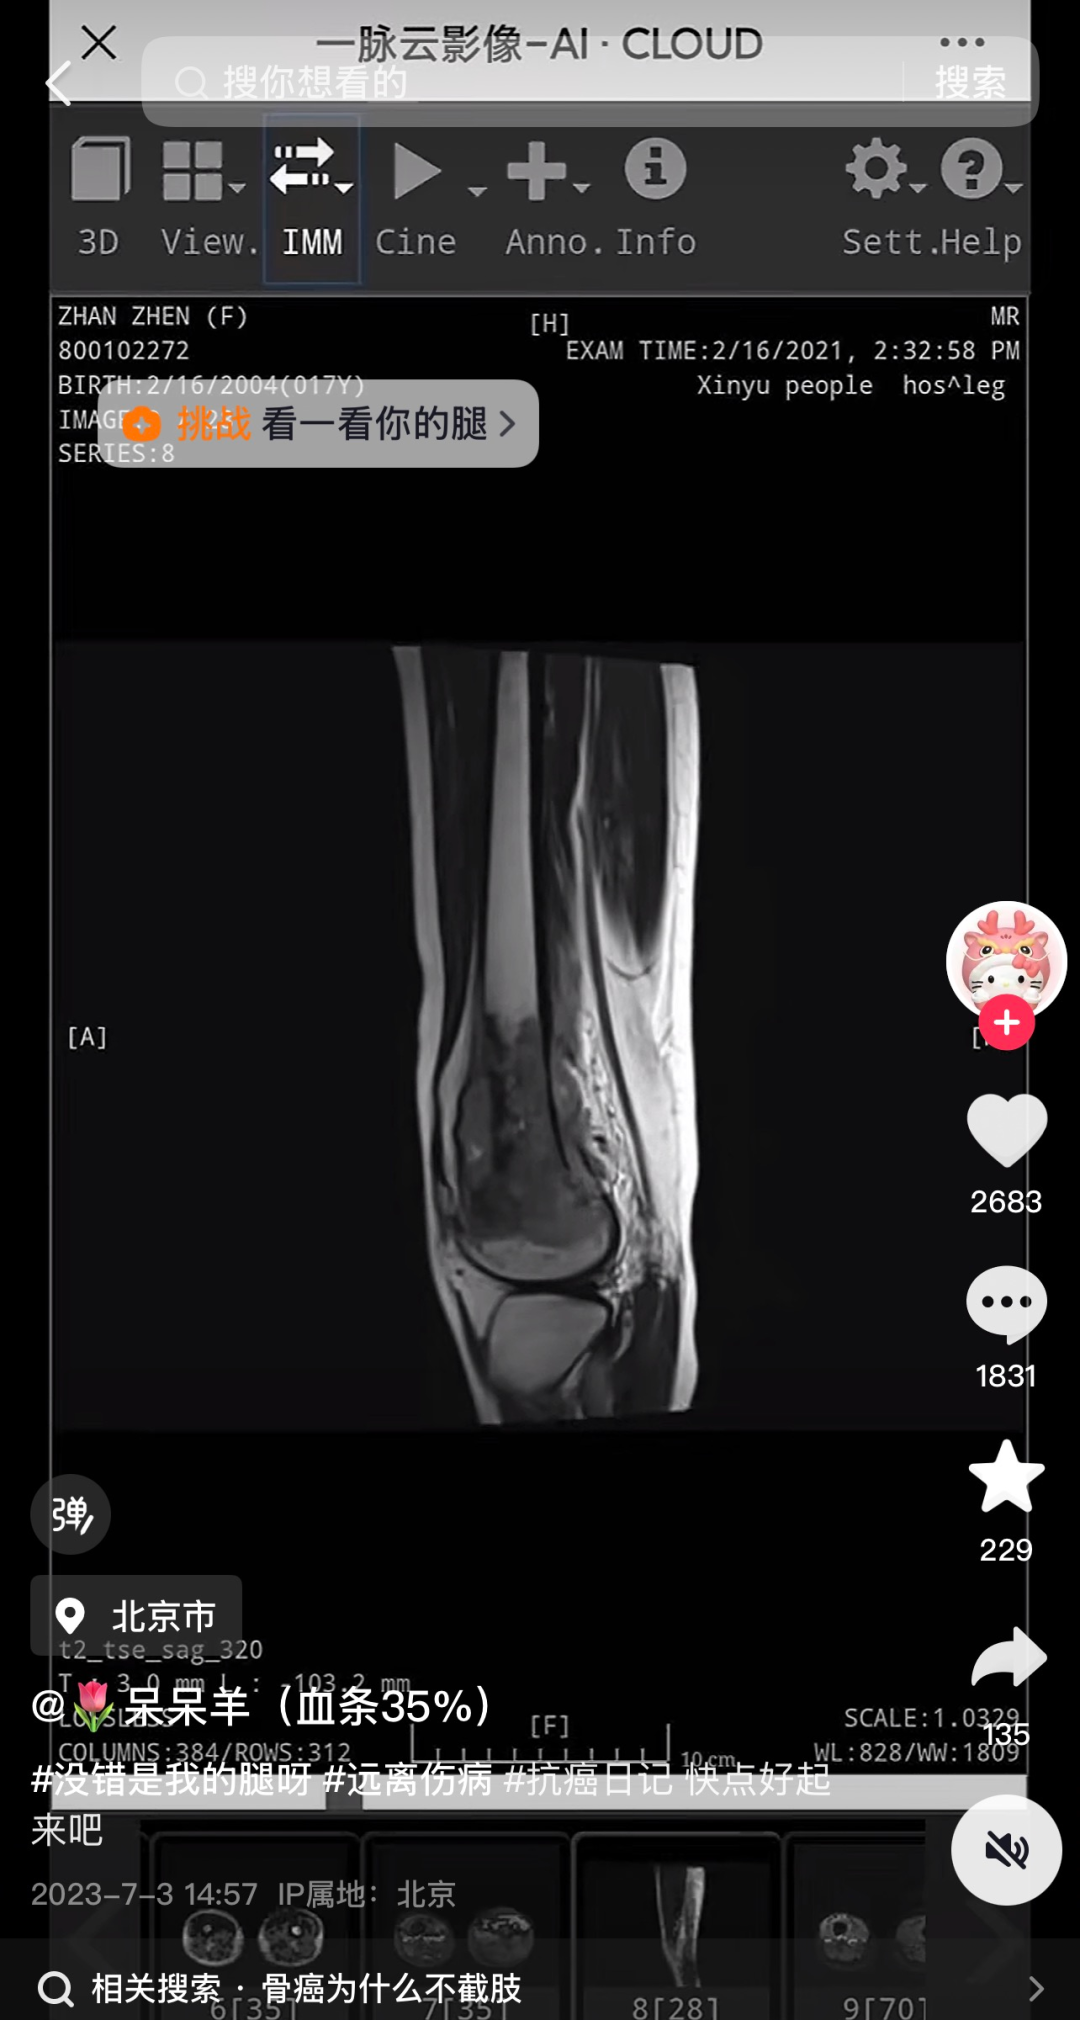

记者发现,网红“呆呆羊(血条35%)”抖音账号有16.7万粉丝,2023年7月3日,“呆呆羊”更新首条实验,视频中“呆呆羊”发布了我方的会诊讲演,时候为2021年2月16日。

在之后的两年更新时候里,“呆呆羊”账号大部分作品是我方的抗癌视频。据悉,“呆呆羊”5年阅历了40次化疗、20次放疗、25次免疫养息、屡次插管,耐久卧床与死神擦肩。其终末一条视频停留在7月15日,多名网友在账号视频下留言抒发哀念念。